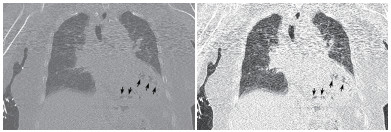

患者女性,75岁。因“被发现晕倒在地伴大小便失禁6 h余”于2018年10月25日12:10入院。患者为独居老人,当晚失联,入院6 h前,家人在家中发现其神志不清,大小便失禁,卧于床边,后患者家属呼120送至本院急诊科。入院后详细追问病史,患者身边无药瓶,家中亦无煤烟味。既往有“冠心病陈旧性心肌梗死、高血压病、2型糖尿病”病史11年余,“卵巢癌术后放化疗”病史2年余,“直肠占位”病史半年余。入院急诊体格检查:体温36.0℃,脉搏80次/min,呼吸17次/min,血压108/52 mmHg(1 mmHg=0.133 kPa),老年女性,神志不清,烦躁,面色苍白,皮肤湿冷、散在花斑,皮肤黏膜无破损。双侧瞳孔等大等圆,对光反射存在,言语、伸舌及肌力检查不合作,双肺呼吸音清,未闻及干湿性啰音,心率80次/min,律齐,心脏各瓣膜听诊区未闻及杂音,肝脾肋下未及,双下肢无水肿,四肢可见不自主活动,双侧病理征未引出。入院后心电图提示肢体导联及胸导联均有T波低平或倒置,V4-V6导联ST段压低(图 1)。血常规:白细胞计数32.35×109/L,中性粒细胞比率84.7%,中性粒细胞计数27.4×109/L,血红蛋白64 g/L,血小板计数221×109/L;CRP 111.9 mg/L,PCT > 100 ng/mL;肌酸激酶1 847 U/L,肌酸激酶同工酶356 U/L,肌酐219 μmol/L,肌钙蛋白T 6 257 pg/mL,NT-proBNP > 35 000 pg/mL。入院后急查颅脑、胸部及全腹CT,胸部CT提示左心室、室间隔及肺动脉根部区域见不规则条状、条片状低密度影,参考CT值约-200~-900 HU(气体密度影),外周伴伪影,左心室为著,外周分布为主,似累及心肌区域,部分心肌变薄,心包区域尚连续,主动脉系统未见气体影(图 2~3)。12:45患者病情急剧进展,呼吸心搏骤停,予气管插管、心肺复苏及药物抢救治疗,13:25抢救无效临床死亡,患者家属拒绝尸检。

| 示气体影以左心室为著,外周分布为主,似累及心肌区域,部分心肌变薄(黑色箭头所示) 图 3 患者胸部CT冠状位影像 |

本例患者恶性肿瘤、糖尿病病史等使患者免疫功能低下,易合并重症急性感染。胸部CT显示左心室、室间隔及肺动脉根部区域见不规则条状、条片状低密度影,测量CT值提示为气体密度影。2016年Laiq等[1]曾报道因感染性心内膜炎致患者左心室内气体形成一例,患者血培养提示柠檬酸杆菌生长,最终患者发生急性心力衰竭,紧急二尖瓣置换术,术后乳头组织同样培养出柠檬酸杆菌,经抗感染治疗预后良好。2014年Alladina等[2]也曾报道一例因播散性肺克雷伯杆菌感染、产气,气体进入血液系统引起的脑空气栓塞。另外,临床工作中某些有创诊疗中,如深静脉置管、肺穿刺活检等也可能引起心脏空气栓塞[3-4]。但本例报道患者脑动脉、主动脉等大动脉系统未见明显气体影,说明患者左心室内气体不具有流动性。仔细观察胸部CT影像学表现,气体在左心室内主要沿室壁分布,部分心肌壁变薄,综合考虑为左室心内膜炎可能。左室内气体位于心内膜下,不在心腔内,故不具备游走性,这也就能解释为何患者其他动脉系统血管内不存在气体的原因。

本例患者存在重症急性感染,烦躁、皮肤湿冷、皮肤散在花斑,提示患者可能存在感染性休克,急性感染累及心内膜、心肌导致心内膜炎、心肌炎,细菌产气引起心内膜下气体形成。但遗憾的是,患者病情进展迅速,患者家属拒绝尸验,无法获得进一步临床资料。死亡原因推测可能为感染性休克,加之感染侵蚀患者心内膜,心肌使心肌变薄,最终引起心脏破裂或心内膜下气体破入心腔内引起空气栓塞而死亡。